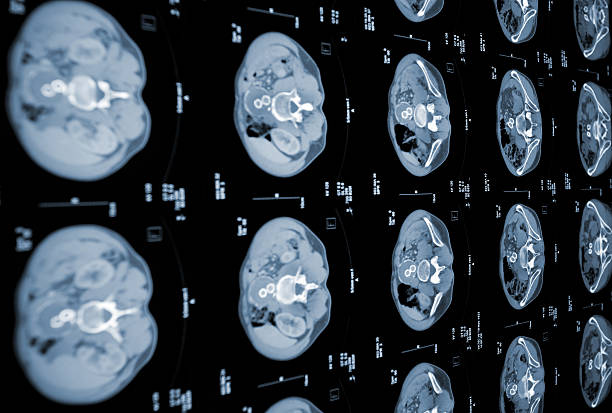

췌장암 초기증상 3. 황달

췌장암 초기증상 두 번째는 황달인데요. 황달은 췌장 머리(췌장 머리)에 암이 발생할 때 대부분의 환자에서 발생해요. 실제로 췌장암 진단을 받은 환자 중 황달로 췌장암을 발견해서 진단을 받는 사례가 많아요.